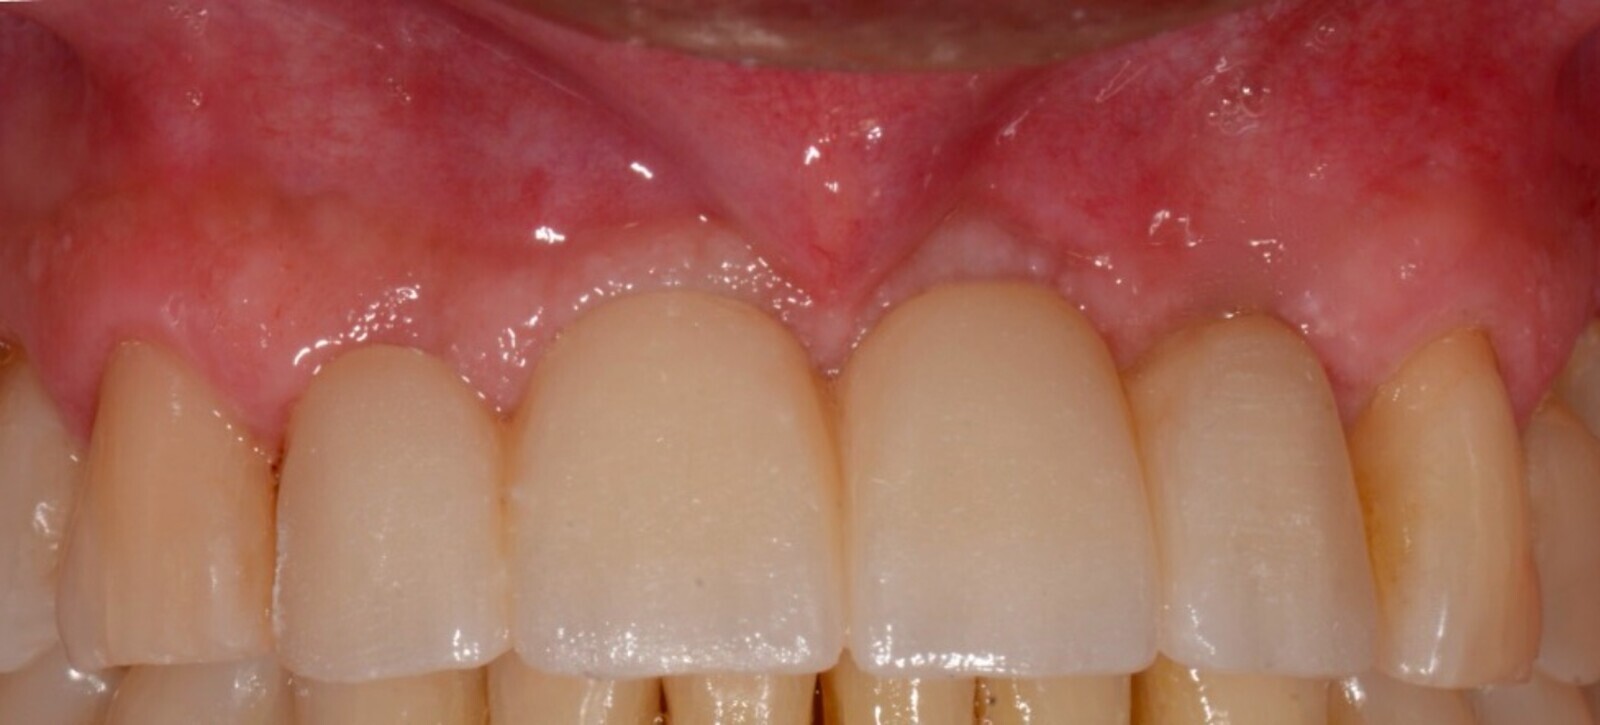

Imagen 5. Resultado final del tratamiento.

En las imágenes se observa el volumen, la regeneración y mantenimiento de las tablas vestibulares de todas las piezas intervenidas, responsables del aspecto de la guirnalda gingival. Sin reabsorción ósea, resultando un tratamiento biológico. “En todo el tratamiento no existe ninguna maniobra clínica, ni del sistema que genere una reacción de defensa que se manifieste como reabsorción, consiguiendo así una integración implanto quirúrgico protético ideal.

Caso donde se observa el volumen, la regeneración y mantenimiento de las tablas vestibulares sin reabsorción ósea, resultando un tratamiento biológico.